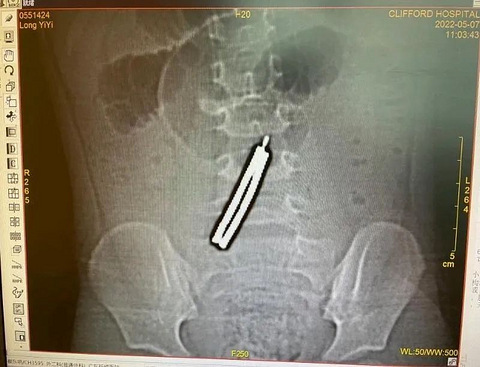

3岁女童误吞这种东西,肠子竟被磨穿5个洞......

近日,广州市3岁半的娜娜(化名)腹痛呕吐,还发高烧,经CT检查发现,她腹中竟藏着10块磁力棒,1颗螺丝钉!异物在消化道“你追我赶”“相互吸引”,串成一个约7厘米的“发夹”,磨穿了5个洞,非常危险。为防止病情恶化,普通外科医生迅速为女童开展手术,将异物顺利取出,终于成功脱险。 女童突然腹痛呕吐 原来是误吞了磁力棒 不久前,家住广州番禺区的女童娜娜接连几天都喊肚子疼,还反复呕吐和发高烧,这可把家长急坏